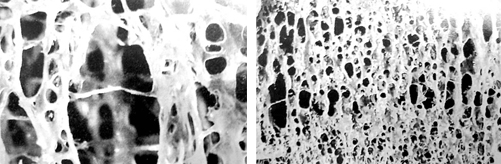

우리 몸이 식생활을 통한 칼슘의 흡수와 소변을 통한 칼슘의 배출 사이에서 칼슘의 항상성이 깨지게 되면 부족한 칼슘은 뼛속에 저장된 칼슘을 끌어다 쓰게 됩니다. 뼛속의 칼슘이 빠져 나가 골밀도가 낮아지면 뼈 조직이 흡사 바람 든 무처럼 옹골차지 못하고 숭숭 하게 되는 것이 바로 골다공증입니다.

골밀도란 뼈의 단단한 정도를 나타내는 것으로 골밀도 수치가 높을수록 뼈가 단단함을 말합니다.